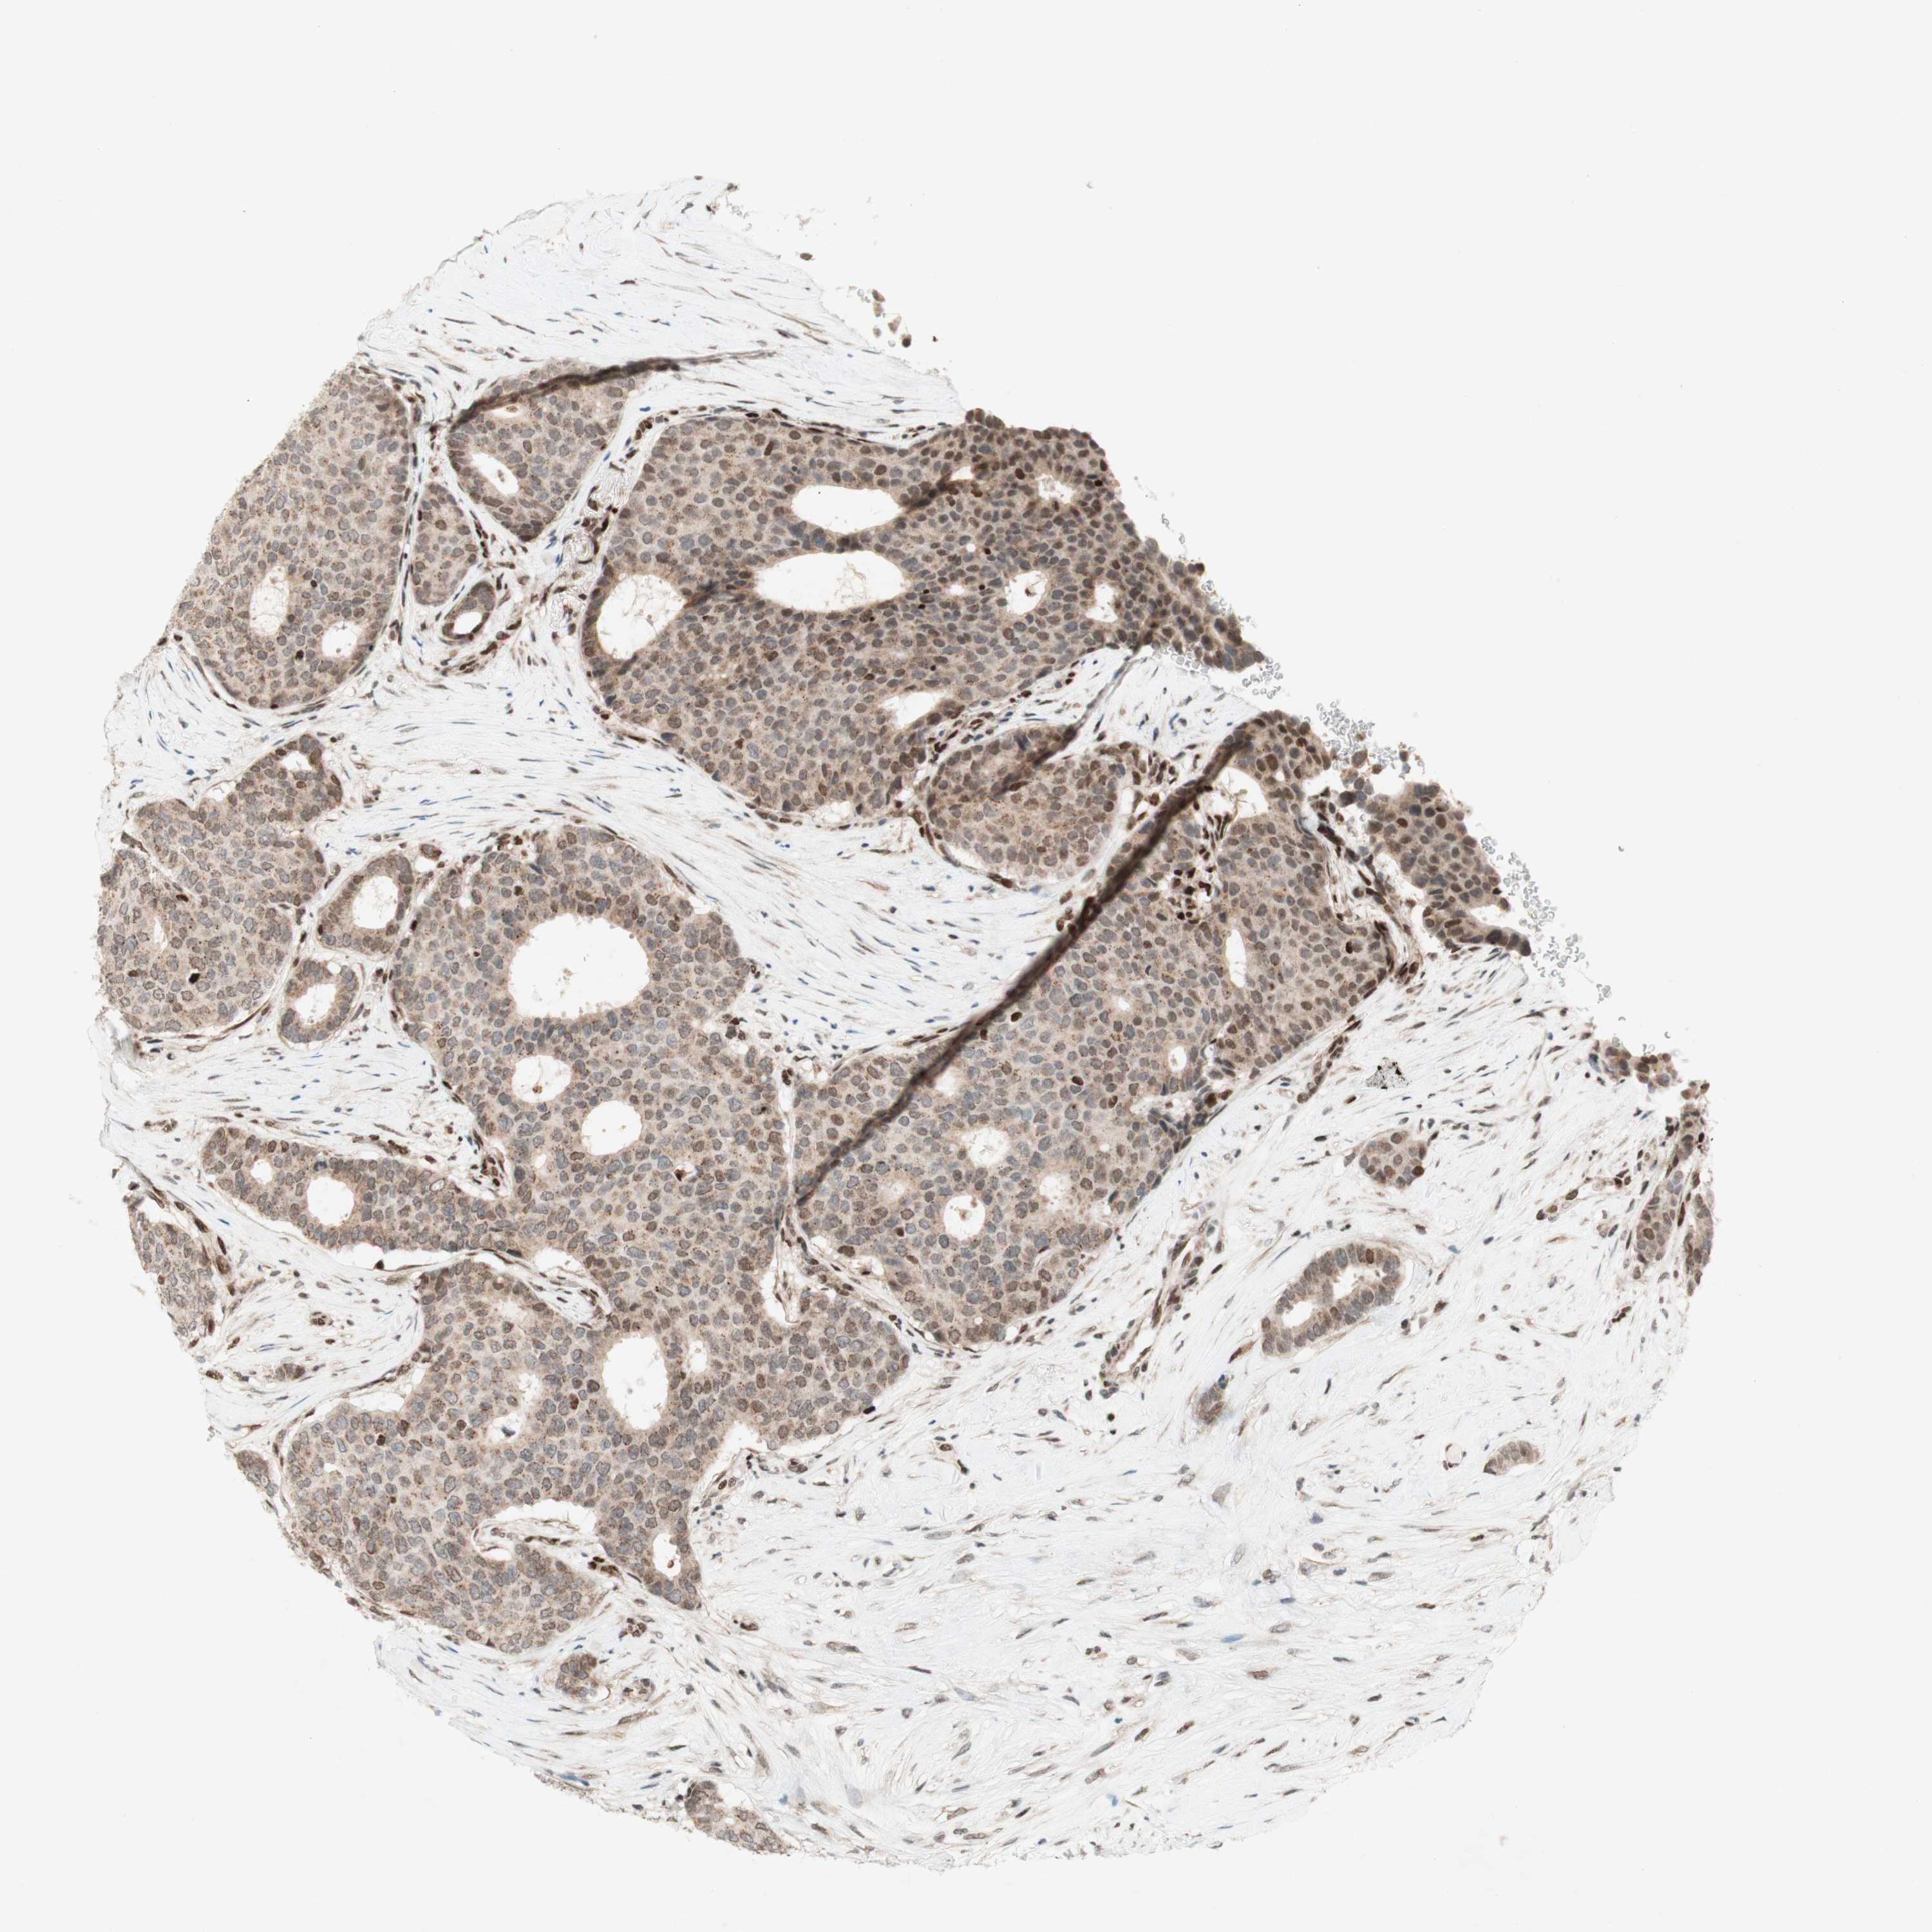

CANCER BREAST CANCER Show tissue menu

BRCA TCGA BRCA VALIDATION PROTEIN EXPRESSION